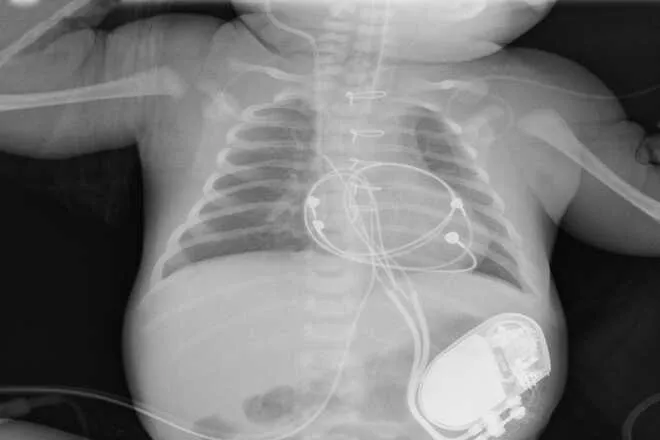

5 родильных залов оснащены аппаратурой для оказания экстренной реанимационной помощи роженицам и новорожденным, кардиотокографами для мониторинга ЧСС плода и маточной активности, аппаратами для мониторинга гемодинамических показателей матери, включая ЭКГ, АД, сатурацию. Послеродовое отделение — на 45 коек, расположено на двух этажах и является самым большим в Перинатальном центре.

Родильные залы оснащены детскими реанимационными столиками, аппаратурой для оказания экстренной реанимационной помощи роженицам и родильницам, кардиотокографами для мониторинга ЧСС плода и маточной активности, аппаратами для мониторинга гемодинамических показателей матери, включая ЭКГ, АД, сатурацию. В отделении для пациенток обеспечена психологическая релаксация с использованием надувных мячей, массажеров, душевых.